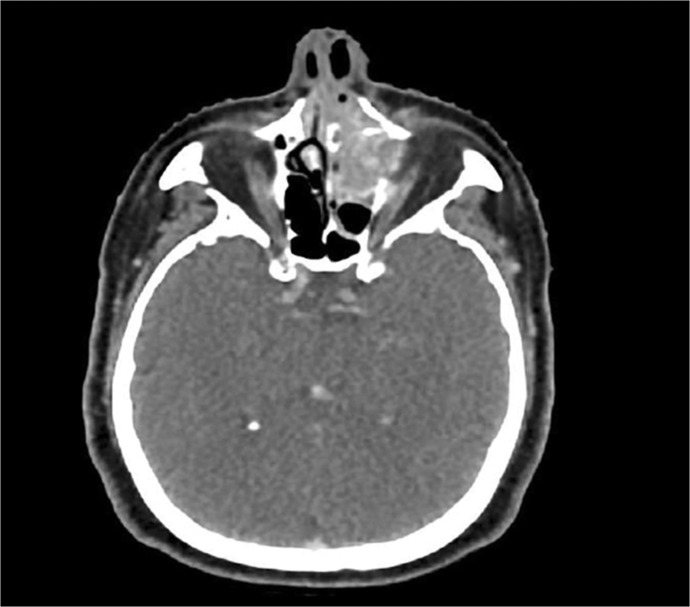

Case presentation: We report the case of a 55-year-old male who presented with bilateral nasal discharge, recurrent epistaxis, progressive nasal swelling, and left-sided epiphora over several months. Clinical examination revealed a grade III reddish, polypoidal mass with nasal obstruction and palpable cervical lymph nodes. Imaging showed a destructive mass involving the nasal cavity and adjacent sinuses. Histopathology and immunohistochemistry confirmed the diagnosis of teratocarcinosarcoma. Surgical resection via lateral rhinotomy and medial maxillectomy, followed by radiotherapy and chemotherapy, led to significant regression of the tumor.